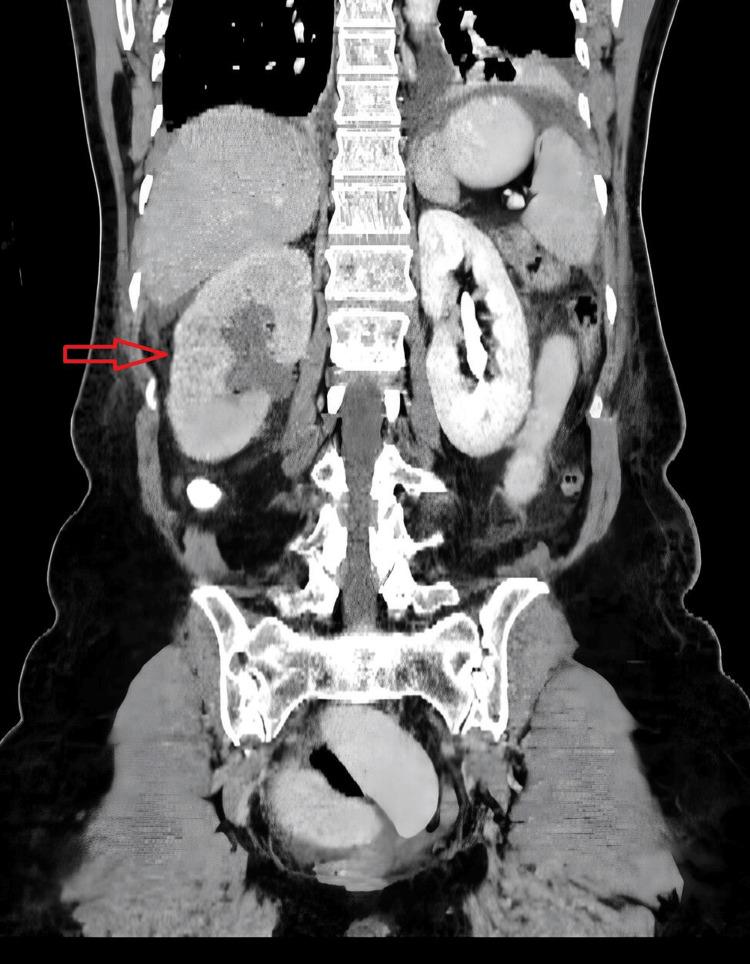

Small bowel obstruction is one of the most common urgent surgical conditions, caused by a variety of factors, with adhesions, malignancies, and hernias, internal and external, being the most common. Many types of internal hernias have been described in the literature; however, internal hernia caused by the ureter as a secondary complication of ureteroplasty is rare and only a few cases have been reported worldwide. This presentation discusses an interesting case of small bowel obstruction accompanied by obstruction of the urinary tract due to an internal hernia caused by the ureter. A 58-year-old female presented to the emergency department (ED) with acute pain in the abdominal and right lumbar region. Her surgical history includes hysterectomy, right ureter injury, and ureteroplasty performed 10 years ago. Clinical examination showed tenderness in the lower abdomen, positive Giordano's sign on the right, and metallic bowel sounds. A computer tomography scan revealed right-sided hydronephrosis, absence of excretion in the right urinary tract, and dilated loops of the small intestine. An exploratory laparoscopy revealed a small bowel loop strangulated by the ureter, followed by laparotomy, resection of a segment of the ileum, oblique anastomosis, and reimplantation of the right ureter. The patient was discharged eight days postoperatively without any complications. This case underscores the significance of surgical history in order to recognize even rarer causes of small bowel obstruction.

小肠梗阻是最常见的紧急外科病症之一,由多种因素引起,其中粘连、恶性肿瘤以及内疝和外疝最为常见。文献中已描述了多种类型的内疝;然而,输尿管作为输尿管成形术的继发性并发症导致的内疝较为罕见,全球仅报道了少数病例。本文介绍了一例因输尿管导致的内疝引起小肠梗阻并伴有尿路梗阻的有趣病例。一名58岁女性因腹部和右腰区急性疼痛就诊于急诊科。她的手术史包括10年前的子宫切除术、右侧输尿管损伤和输尿管成形术。临床检查显示下腹部压痛、右侧乔达诺征阳性以及金属样肠鸣音。计算机断层扫描显示右侧肾积水、右侧尿路无排泄以及小肠肠袢扩张。腹腔镜探查发现一段小肠袢被输尿管绞窄,随后进行剖腹手术,切除一段回肠,行斜行吻合,并重新植入右侧输尿管。患者术后八天出院,无任何并发症。该病例强调了手术史对于识别小肠梗阻更罕见病因的重要性。